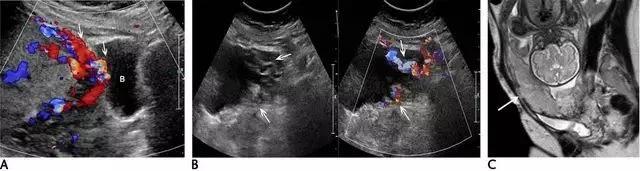

滋养层胎盘肿瘤包括一组源于胎盘滋养组织的相关肿瘤,如部分性及完全性葡萄胎、侵袭性葡萄胎、绒癌、胎盘滋养层肿瘤。引起本病的风险因素包括高龄孕妇与既往患过胎盘滋养层肿瘤病史。部分或完全性葡萄胎是良性病变,部分性葡萄胎伴有胎儿存活,而完全性葡萄胎没有胎儿,其患绒癌的风险性更大。在超声上,葡萄胎的子宫增大,部分性葡萄胎的子宫可见多个弥漫性无回声病变,胎儿因多发先天性畸形、三倍体及生长受限而不能存活(图 16)。

图 16 示部分性葡萄胎:A 为子宫横断面,箭头示宫内不均质囊实性包块,血流丰富,宫内可见积液。B 示宫内另可见部分胎儿(小箭头)及较短的脐带(长箭头、)。C 为盆腔矢状位的压脂像 T2WI,上方箭头示宫内不均质包块,下方箭头示部分胎儿